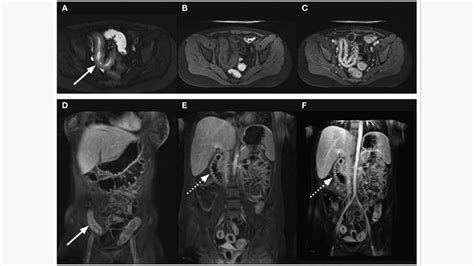

RMN Pelvin

RMN-ul pelvin este o investigație imagistică avansată care oferă imagini detaliate ale structurilor interne ale pelvisului și ale țesuturilor învecinate. Aceasta include vezica urinară, organele de reproducere masculine (prostata, testiculele) și feminine (uter, ovare), ganglionii limfatici, intestinul subțire și gros, precum și oasele pelvine.

Când este Recomandat RMN-ul Pelvin?

Investigația este indicată pentru evaluarea extinderii locale a diferitelor tipuri de cancer, planificarea tratamentului și monitorizarea evoluției pacientului. Este utilă în determinarea stadiului cancerelor de ovar, col uterin, uter, vezică urinară, rect, prostată și testicular.

Indicații Specifice pentru RMN Pelvin

- La femei: Sângerări vaginale anormale; masă pelviană detectată clinic sau imagistic; fibroame; masă pelviană identificată în sarcină; endometrioză confirmată după ecografie; durere abdominală inferioară; infertilitate inexplicabilă (după ecografie); durere pelviană persistentă inexplicabilă.

- La bărbați: Noduli sau umflături la nivelul testiculelor/scrotului; testicul necoborât neidentificat la ecografie; durere pelviană; tulburări urinare inexplicabile.

- Comune ambelor sexe: Anomalii vizibile la radiografia pelvisului; malformații congenitale ale șoldurilor; traumatisme sau leziuni ale șoldului; durere de șold inexplicabilă.

Uro-RMN

Uro-RMN-ul este o metodă imagistică avansată, neiradiantă, care permite vizualizarea detaliată a aparatului urinar (rinichi, uretere, vezică urinară) și, în anumite situații, a prostatei.

Entero-RMN

Entero-RMN-ul (sau enterografia RMN) este o metodă imagistică avansată, neinvazivă și fără radiații, utilizată pentru evaluarea detaliată a intestinului subțire și a structurilor din jur.